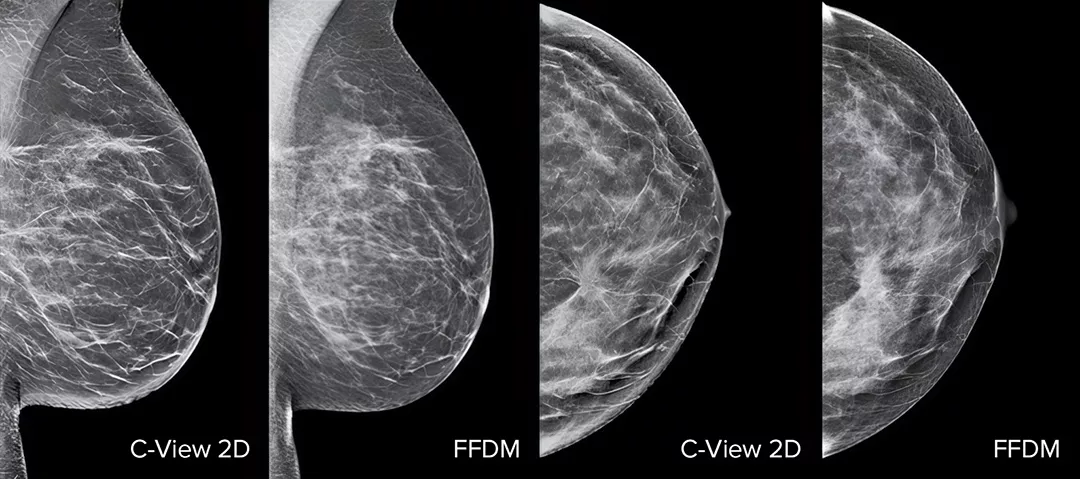

Images of breast x-ray

Architectural distortions, mass lesions, and bright spots commonly found in microcalcifications are more visible in the C-View 2D image than on the traditional FFDM 2D images or tomo slices.4,6-9

Architectural distortions, mass lesions, and bright spots commonly found in microcalcifications, are more visible in the C-View 2D image than on the traditional FFDM 2D image or tomo slice.4,6-9